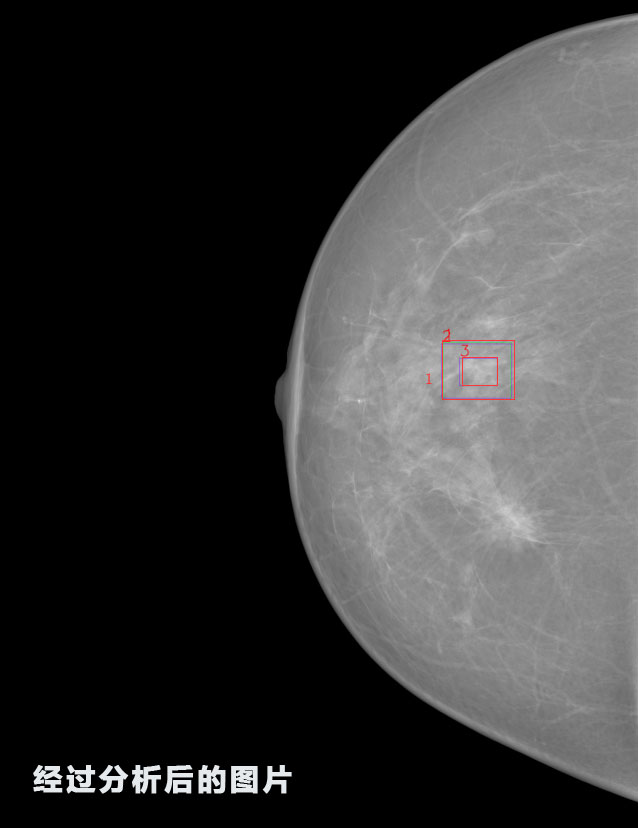

識(shí)別報(bào)告:

1.發(fā)現(xiàn)良性鈣化,可能性為19.88%---位置框指數(shù):[1796.0867 1359.8237 2058.1372 1582.5334]

2.發(fā)現(xiàn)惡意鈣化的可能性為15.18%---位置框指數(shù):[1789.4733 1365.9951 2063.7698 1576.0613]

3.發(fā)現(xiàn)惡意鈣化的可能性為12.45%---位于框指數(shù):[1859.3987 1422.3184 2006.5494 1528.2698]